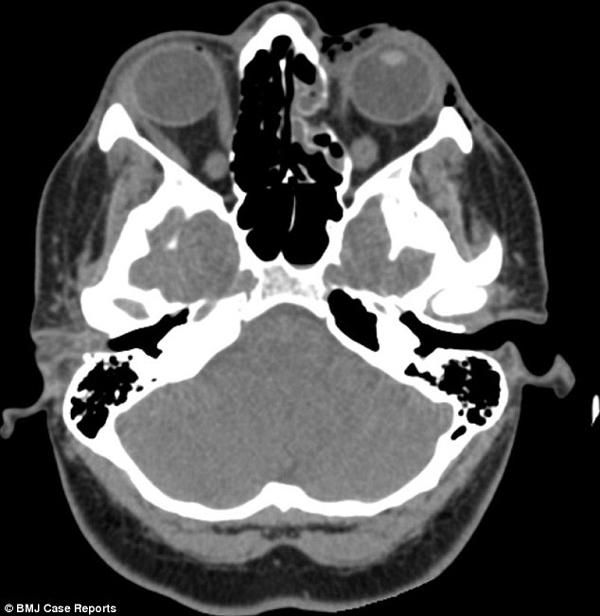

Tại Bệnh viện Đại học North Middlesex, sau khi chụp chiếu và khám kỹ lưỡng, các bác sĩ chẩn đoán cô bị gãy xương trong mắt trái và đây là một thương tích rất hiếm khi xảy ra. Mặc dù tầm nhìn của cô bị suy giảm và xương mắt bị gãy nhưng may mắn các chuyển động và bộ phận khác vẫn bình thường.

Các chất nhầy chảy tràn vào mũi bên trái tạo thành khoảng đen trên phim chụp.

Lý giải về nguyên nhân khiến cho người phụ nữ bị gãy xương trong ổ mắt, Tiến sĩ Sam Myers, bác sĩ tại Bệnh viện Đại học North Middlesex cho biết khi xì mũi, người phụ nữ đã vô tình làm tăng áp lực trong xoang khiến xương bị gãy. Đồng thời chính điều này đã khiến cho các chất nhầy rò rỉ vào đường hô hấp và trong mô quanh mắt.